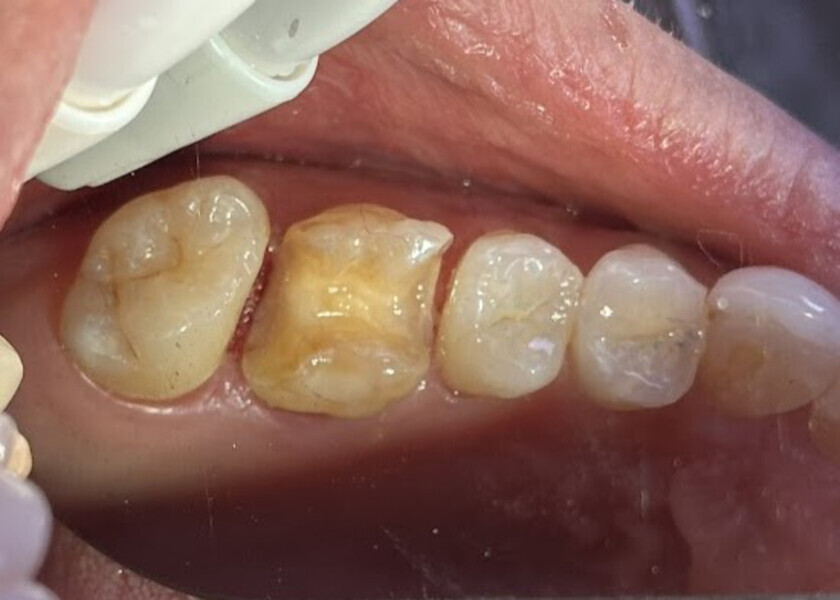

Fig. 19: Clinical view of the old composite restorations with recurrent caries on the molars and premolars.

A 23-year-old female patient presented with cold sensitivity of the teeth in the maxillary right posterior sextant. Examination noted old composite fillings in the molars and premolars and recurrent caries on each tooth (Fig. 19). A bitewing radiograph was taken to evaluate the extent of the recurrent caries and the dimensions of the composite restorations (Fig. 20). Owing to the dimensions of the restorations and caries, inlay and onlay restorations were suggested to restore the teeth and preserve tooth structure as an alternative to complete crowns. The patient’s questions were answered, and she agreed to the proposed treatment. She was informed that the treatment could be completed in a single appointment utilising 3D printing for restoration fabrication. Time in the schedule permitted treatment to be performed during that same appointment. Our intent is to provide conservative restoration with superior accuracy and definition compared with milling, as well as better predictability and mechanical properties compared with direct resin composite restorations.